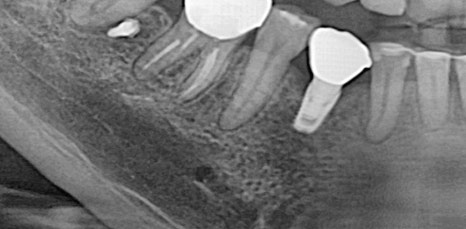

특히 위쪽 어금니 쪽이 상실 되어 임플란트 시술을 진행해야 하는데 잇몸 뼈가 부족한 상태라면 추가적으로 상악동거상술을 함께 진행해야 했어요. 상악동이란 코 양옆에 위치하고 있으며 뼈 속에 비어 있는 공기 주머니로 두개골의 무게를 줄여주는 곳이었어요. 상악동은 아주 얇은 막으로 둘러 쌓여 있으며 상악 쪽의 잇몸 뼈가 부족한 상태로 임플란트를 식립 하게 된다면 상악동 막이 찢어지거나 천공이 생길 수 있었어요.

상악동에 천공이 생기게 된다면 염증으로 인해 부작용이 생길 수 있었어요. 그렇기 때문에 환자 개개인마다 크기와 위치가 모두 다른 상악동의 위치와 잇몸 뼈의 두께를 정확히 파악하는 것이 중요했어요. 정밀 검사 후 임플란트를 식립 하기에 잇몸 뼈의 양이 부족하다는 진단이 나오게 된다면 얇은 상악동 막을 들어올려 준 후 필요한만큼의 뼈 이식을 진행해 주는 방법이 상악동거상술이었어요.

신논현역임플란트에서 말하는 상악동거상술은 치조정접근법과 측방접근법인 두가지 방법으로 진행할 수 있었어요. 남아 있는 잇몸 뼈의 양에 따라 이식 해야 하는 양이 달라지고 그로 인해 상악동에 접근 하는 방법을 기준으로 두가지 방법은 나눠 지고 있었어요. 먼저 치조정접근법은 잇몸 뼈가 4-8mm 정도 확보 되었을 때 사용하는 방법으로 치아가 상실 된 위치의 잇몸에 작은 구멍을 뚫어 준 뒤 그 구멍을 통해 상악동 막을 들어 올린 후 뼈 이식을 진행하는 방법이었어요.

작은 절개 범위와 뼈 이식 양이 많지 않기 때문에 수술 시간이 짧고 통증과 붓기도 적으며 회복 속도 또한 측방접근법에 비해 빠른 편이었어요. 반면 측방접근법은 잇몸 뼈가 4mm 이하로 많은 양의 잇몸 뼈를 이식 해야 할 때 필요한 방법이었어요. 잇몸 측면에서 큰 창 모양으로 절개 후 접근하는 방법으로 수술시간이 길고 붓기, 통증이 큰 편으로 회복 속도 또한 더딘 편이었어요.

하지만 시야 확보가 잘 되어 출혈과 돌발 상황에 대한 대처를 빨리 할 수 있어 안전하게 수술을 마무리 할 수 있다는 장점이 있었어요. 치조정접근법과 측방접근법 두가지 방법 중 어떠한 방법이 더 유리하고 안전하다고 할 수 없으며 치조골의 상태와 식립 해야 하는 임플란트의 개수, 상악동의 위치와 두께 등을 고려하여 환자분께 적합한 방법으로 상악동거상술을 진행 하는 것이 가장 안전하고 좋은 방법이라고 할 수 있었어요.